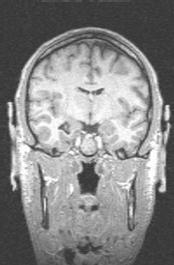

During the summer of 2000, I participated in an fMRI (functional magnetic resonance imaging) study at the University of Virginia.  An fMRI scan shows not only the structure of the brain, but which parts are currently active.  By asking people to do different things while being scanned, psychologists are able to figure out which parts of the brain are used for different tasks.

Since I was working with the psychologists at the time, I was not paid to participate in the study.  However, I volunteered to do it anyway in order to help out my friends, advance mankind's knowledge, and get really cool pictures of what my brain would look like if my head were chopped in half.  Enjoy!

Coronal view